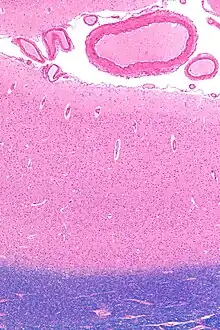

The primary visual cortex, which is defined by its function or stage in the visual system, is approximately equivalent to the striate cortex, also known as Brodmann area 17, which is defined by its anatomical location. The name "striate cortex" is derived from the line of Gennari, a distinctive stripe visible to the naked eye[11] that represents myelinated axons from the lateral geniculate body terminating in layer 4 of the gray matter.

The primary visual cortex is divided into six functionally distinct layers, labeled 1 to 6. Layer 4, which receives most visual input from the lateral geniculate nucleus (LGN), is further divided into 4 layers, labelled 4A, 4B, 4Cα, and 4Cβ. Sublamina 4Cα receives mostly magnocellular input from the LGN, while layer 4Cβ receives input from parvocellular pathways.[12]